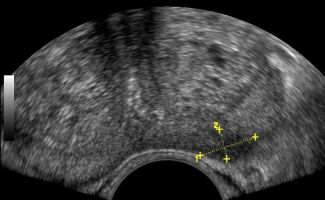

- Prostate: It allows for a detailed assessment of the prostate's morphology and size.

- Peripheral Prostate Zone: The exam can detect focal lesions, such as neoplasms, in the peripheral zone of the prostate.

- Central Prostate Zone: The central zone can be checked for the presence of inflammation, abscesses, calcifications, or other space-occupying lesions.